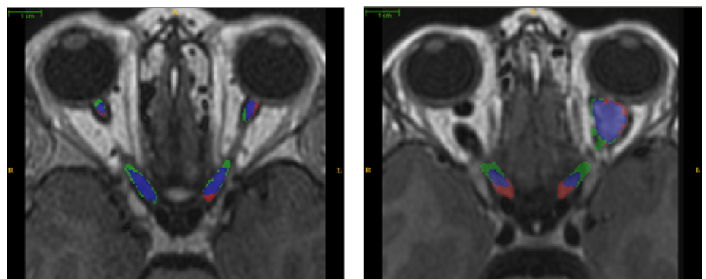

Depending on severity, pathological AVPs can have a drastically different local shape and appearance characteristics than healthy ones, thus failing the shape model based segmentation methods in cranial nerve pathways. To illustrate, Fig 1(a) demonstrates a healthy optic nerve along with a contralateral optic nerve having OPG. Fig 1 (b)-(c) show the renderings of cases with OPG in optic nerve region. In this paper, we propose, PAScAL, an optimally partitioned statistical shape model with sparse appearance learning for the segmentation of AVPs for both healthy and pathological cases. The challenge of segmenting larger anatomical structures with pathologies have been addressed numerously in the literature [5]. However, development of similar approaches for smaller vascular structures, such as the AVP, have traditionally been ignored. By illustrating the robustness of PAScAL to segment AVP with OPG, we demonstrate the applicability of the proposed method in segmenting other anatomical structures of similar characteristics.

After Institutional Review Board approval, 15 pediatric MRI scans with healthy AVPs and 6 with OPG were acquired for this study. The acquired data were T1 weighted cube with Gadolinium contrast enhancement having spatial resolution between to . The manual ground truth for optic pathway segmentation was created by an expert neuro-radiologist and an expert neuro-ophthalmologist. During the training stage, the dataset was affinely registered to a randomly chosen reference image using a two-stage hierarchical approach: first by optimizing the registration parameters for the entire brain and later by optimizing over the region of interest around the optic nerve. The surfaces for each training instance were computed using the tetrahedral mesh generation approach followed by point set registration to the reference surface. Based on our training set, optimal number of partitions were found to be 12. Three hierarchical scales for shape model and appearance were used. The refinement model was learned on-the-fly from the initial segmentation using a patch of size voxels at the coarsest level. The normalized derivative, the tissue intensity probability, and the tubular structure probability were used together as a unified feature set of size 33 to train the refinement model. To learn the sparse dictionary, co-occurrence features were extracted with an offset of 1 and four directions (, , , ). The co-occurrence features presented in Section 2.3 are then calculated for each direction. During the testing stage, the test image was first registered to the randomly selected reference set followed by automatic overlapping partitioning. The mean shape of the training set was used to initialize the shape model. Fig. 3 shows the qualitative results of PAScAL against the ground truth manual segmentation.